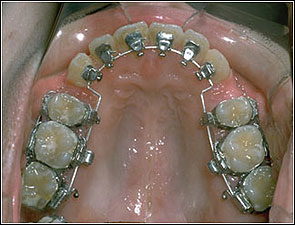

STEP 1. Leveling

TMA018, 0175*0175